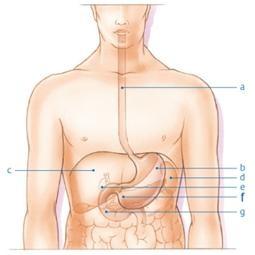

Figuur 1: (A) slokdarm (B) maag (C) lever (D) milt (E) galblaas (F) alvleesklier (G) dunne darm © 2013 KWF Kankerbestrijding